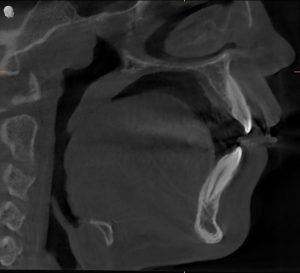

Through clinical examination and radiographic evaluation, we confirmed:

It wasn’t a structural problem — it was habitual mouth breathing.

- Agasthya’s Progress:

His nasal breathing normalized, facial muscle tone improved, and his teeth grinding reduced significantly. He didn’t need further expansion. - Abhaya’s Response:

While breathing improved, she still had a narrow palate and limited airway volume — so we proceeded with palatal expansion to support her growth and bite alignment.